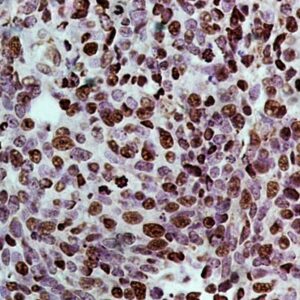

BioGenex has pioneered the development of miRNA research and diagnostics tools with leading-edge products. Currently, we offer over 240 ready-to-use (RTU) Super Sensitive™ Nucleic Acid (SSNA) miRNA ISH probes for accurate and early tumor diagnosis. These probes are sensitive enough to detect low-abundant miRNA(s) that are often required to identify biomarkers. They have a high melting temperature enabling stringent washes to remove non-specific binding. BioGenex miRNA probes are dual-end labeled with an anti-fluorophore to amplify the signal and yield clean and intense staining.